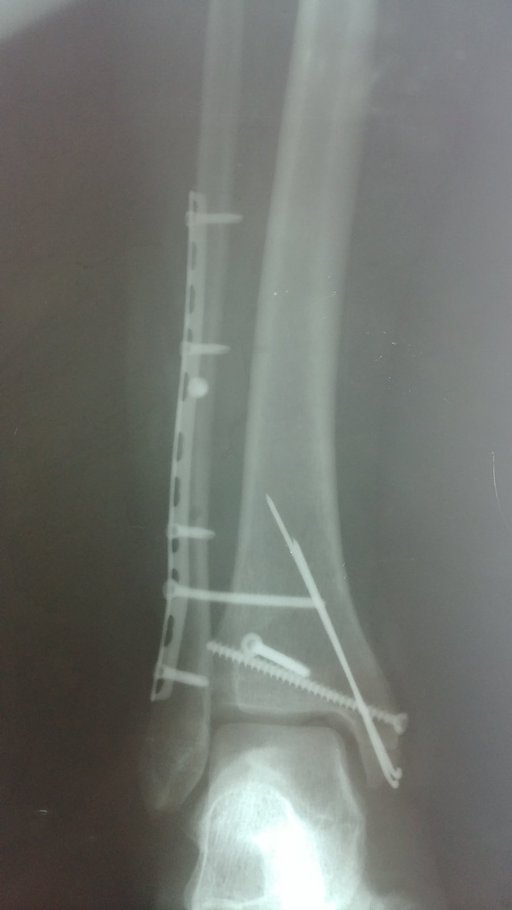

Хвора О. звернулася в травмпункт КНП ТМКЛШД через 5 години після травми яку отримала в побуті при падінні зі стільця. Оглянута травматологом травмпункту, направлена на рентгенографію. Згідно даних рентгенограм встановлено діагноз: Закритий перелом обох кісточок правої гомілки та заднього краю в\гомілкової кістки зі зміщенням уламків. Розрив ДМГС справа. Хворій накладено тимчасову фіксацію та направлено в приймальне відділення КНП ТМКЛШД. Хвора повторно оглянута травматологом стаціонару. При огляді відмічається виражений набряк, біль, порушення функції н\кінцівки. Встановлено діагноз : Закритий перелом обох кісточок правої гомілки та заднього краю в\гомілкової кістки зі зміщенням уламків. Розрив ДМГС зліва. Оскільки на момент огляду у хворої відмічався незадовільний стан м’яких тканин хворій було запропоновано проміжне оперативне втручання з фіксацією г\ступневого суглобу в АЗФ або проміжне лікування системою скелетного витяжіння. При госпіталізації проведено необхідні інструментальні та лабораторні методи обстежень. Хвора відмовилася від накладання АЗФ. Вибрано метод лікування скелетним витягом. Під час перебування у відділенні хвора отримувала протинабрякову терапію, знеболюючі препарати, антикоагулянти. На 8-му добу лікування скелетним витягом набряк спав, м’які тканини перебували в задовільному стані. Хворій проведено демонтаж ССК. Та проведено оперативне втручання: Відкрита репозиція з МОС перелому зовнішньої кісточки пластиною LCP та відкрита репозиція з МОС внутрішньої кісточки спицею та гвинтом. Фіксація ДМГС позиційним гвинтом. Після оперативного втручання хвора переведена в палату. З 2-3 доби хворій дозволено активні рухи у г\ступневому суглобі без навантаження на праву н\кінцівку. Шви знято на 12 добу, хвора в задовільному стані з наданими рекомендаціями щодо тактики подальшого лікування та реабілітації виписана з травматологічного відділення.